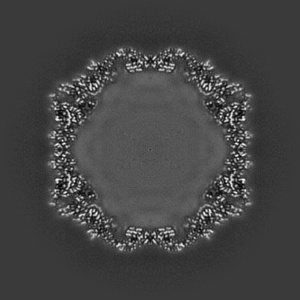

EMD-19774

Coxsackievirus A9 bound with compound 20 (CL300)

Single-particle2.26 Å